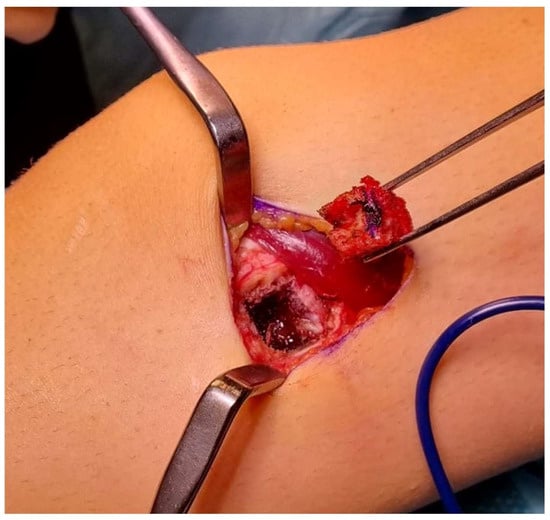

2.3. Incisional Biopsy

| Open incisional biopsy | When adequate tissue sample cannot be obtained with closed biopsy. When accurate histological diagnosis and grading is required to decide for preoperative chemotherapy or radiation therapy. When closed biopsy does not correlate with the clinical presentation and imaging. If non-diagnostic closed biopsy. Can be used with frozen sections. Use the smallest incision that is compatible with obtaining adequate specimen. Careful hemostasis (use tourniquet; very rarely use drains). |

| Open biopsy approach | Longitudinal incision. Contamination of one anatomic compartment. Excisable biopsy tract. Meticulous hemostasis. Drain, if necessary, exit in line with skin incision. |